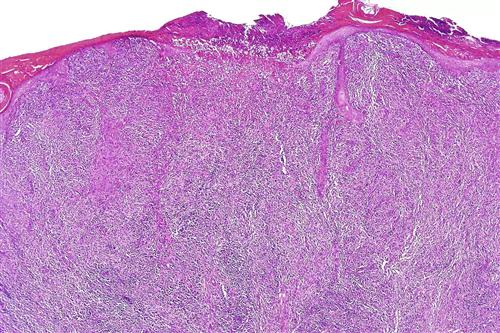

相关图片